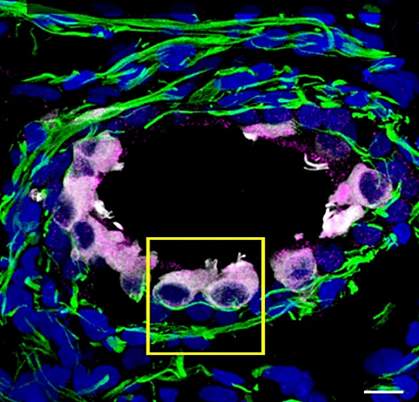

The team obtained similar results from experiments in inner ear organoids. These are 3D tissues generated from stem cells. They mimic not only the types of cells in the inner ear, but also their spatial organization and function. Hair cell- and Schwann cell-like cells in these organoids had the proteins needed for SARS-CoV-2 infection. The virus was able to infect the hair cell-like cells in the organoids.